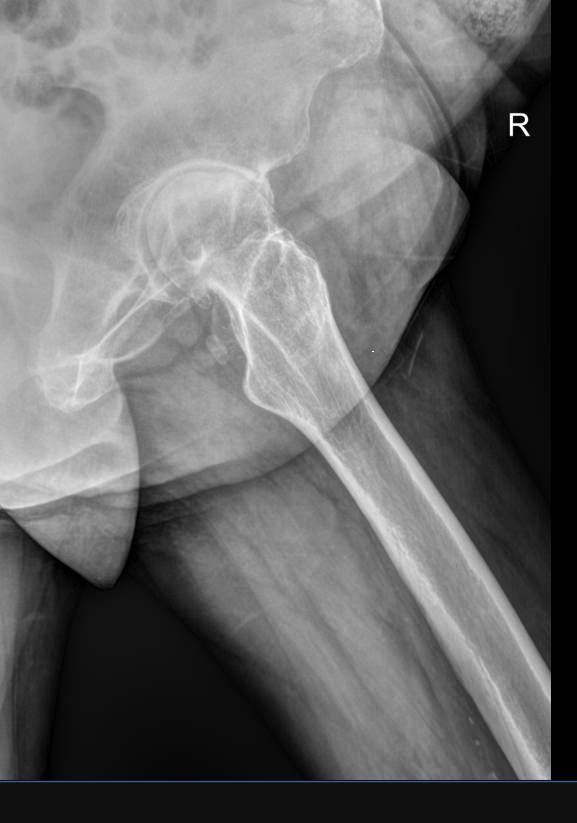

Рентгеновское исследование ― первичный вид диагностики, который назначают при переломах и подозрении на патологию костной ткани. Это неинвазивная, широко доступная и высокоинформативная процедура, во время которой пациент не испытывает никаких ощущений. Полную информацию о состоянии обследуемого участка тела можно получить уже через 10 минут после обследования. При этом современные рентгеновские аппараты излучают минимум ионизирующего излучения, позволяющие безопасно делать множество снимков в год, например, для контроля и коррекции проведенного лечения.

Что показывает рентген обеих бедренных костей в одной проекции

• Травматические повреждения одной или обеих костей ― место перелома, осколки;

• Участки изменений костной ткани, такие как воспаление, гнойное или асептическое, разрежение, размягчение, склерозирование или новообразования;

• Участки поражения мягких тканей, например, кисты, другие новообразования или миозиты, протекающие с оссификацией мышцы.